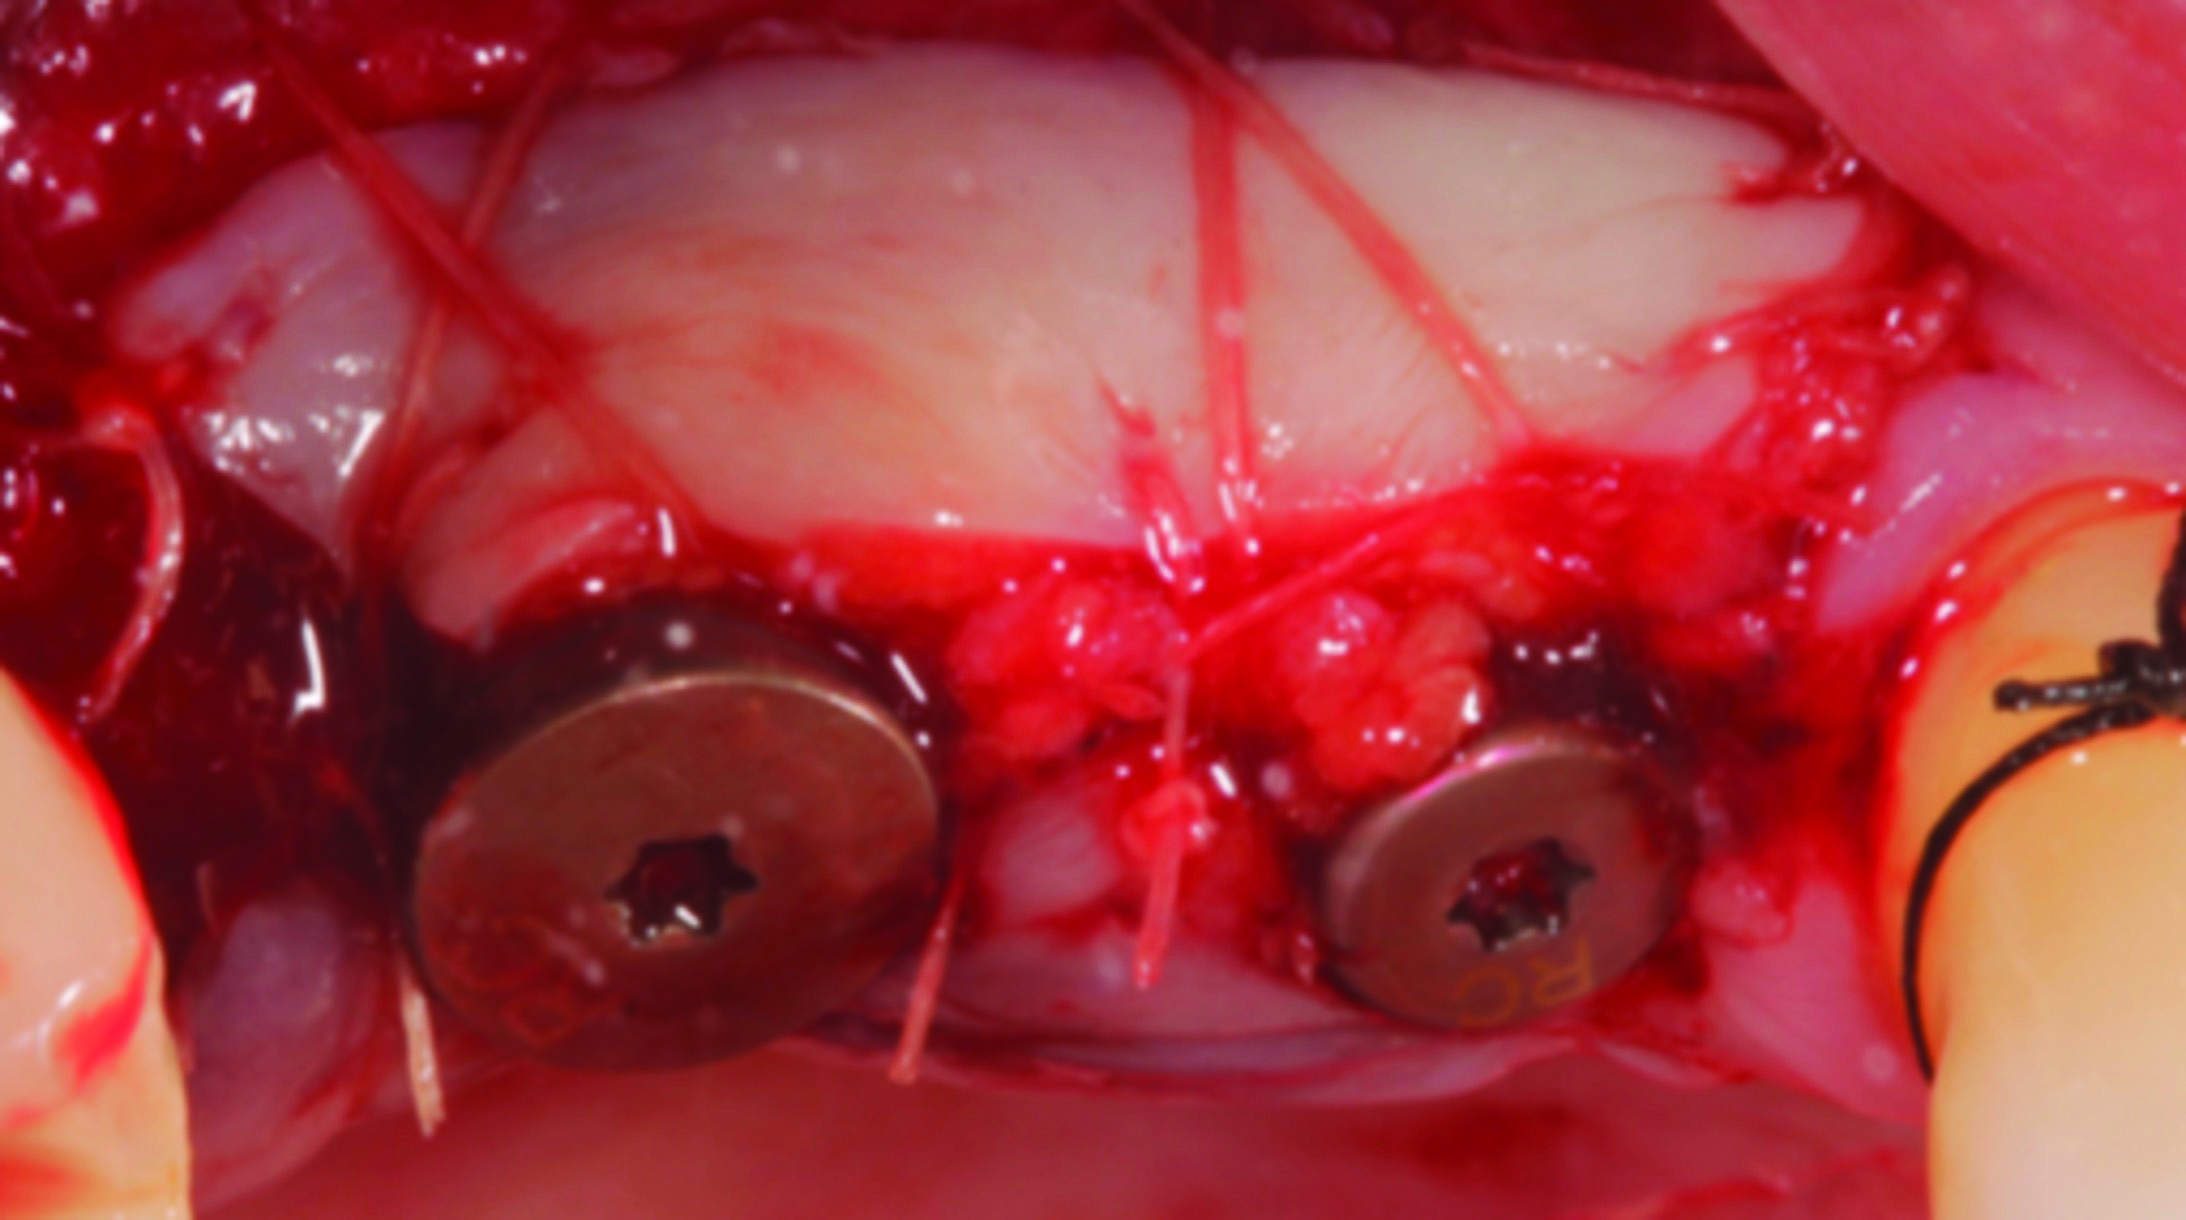

Fig 6 through Fig 8. Example of increasing KMW with an APF at implant uncovery. Fig 6: initial presentation showing lack of KMW; Fig 7: healing abutment placement with APF; Fig 8: 2 months post-treatment. (The dotted lines indicate the MGJ.) Fig 9 through Fig 11. Example of increasing KMW with an APF and FGG at implant uncovery.

Fig 9: initial presentation;

Fig 10: healing abutment placement with FGG; Fig 11: 2 months post-treatment.